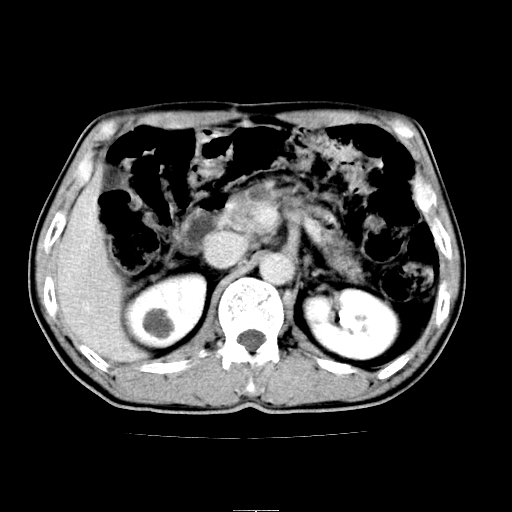

患者男,64岁,胃癌术后三个月,无明显不适。请讨论一下胰头前方小圆形低密度影为淋巴结还是肠管?

增强第6幅图上有气液平相通,是肠管,右肾低密度灶形态不规则似有壁结节,不除外转移.

应该考虑是肠管,理由1、平扫和增强对比,形态和内部的密度有明显改变。2、增强图片可见明显气液平面。

是肠管,右肾低密度灶形态不规则、密度不均匀,不除外转移.

是肠管影。还有右侧肾盂旁囊肿。

另外,胰腺体部密度在平扫和增强时均不太均匀,似有数个小的囊状低密度区存在。不知道增强时其他期如何?应该高度警惕为转移性病变。

胰头右侧低密度影卡考虑为肠管;胰头前部低密度影,增强环形强化,结合临床首先考虑转移灶,其次考虑淋巴结结核(中心干酪性坏死)。

如是转移灶强化多为均质强化。如是结核应见到完整的壁且壁略厚。如是转移虽壁可不完整但内壁应该不规则。所以不支持是结核或转移。敬请指正!